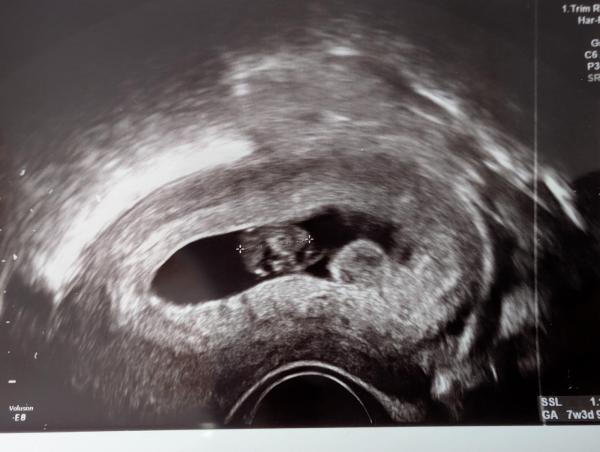

Hallo,  ich war gestern beim 1. Ultraschall bei 7+3.  Neben dem Embryo war eine weitere Wölbung, dort gab es keinen Herzschlag somit kein Zwilling.  Beim Embryo selbst ist alles in Ordnung und zeitgemäß entwickelt.  Die Ärztin vermutet, dass die Wölbung eine Nebenplazenta ist.  Hatte das jemand und hat man es in der 8. SSW schon gesehen?  Mache mir jetzt natürlich Gedanken und es gibt mir keine Ruhe. Nächster Termin ist erst in 4 Wochen.  Oder sollte ich auf einen früheren Termin bestehen?